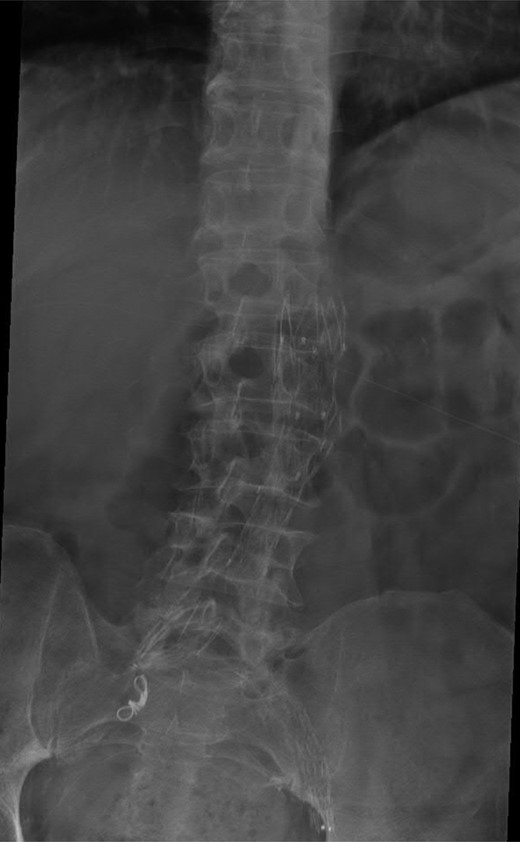

A 74-year-old male was admitted with an intracapsular fractured left neck of femur (Fig. 1). According to the NICE guidelines, he received a cemented THR (Fig. 2) via the posterior approach in the lateral decubitus position. Five weeks prior, he had an EVAR for a leaking AAA. Due to a calcified, narrow right common iliac artery (CIA), the EVAR consisted of a left aortouniiliac endograft with coil embolization of the right CIA and a femoro-femoral crossover graft (Figs 3 and 4).

AP radiograph of the lumbar spine demonstrating the aortouniiliac EVAR with coil embolization of the right CIA.